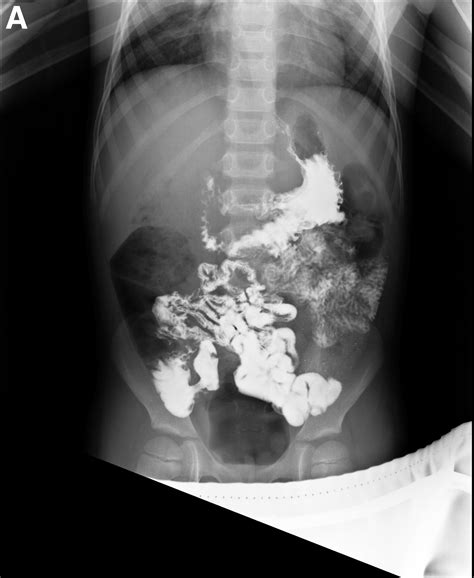

Meckel’s Diverticulum on Small-Bowel Follow-Through Series and Computerized Tomography Scan in a ...

TitleMeckel’s Diverticulum on Small-Bowel Follow-Through Series and Computerized Tomography Scan in a ...